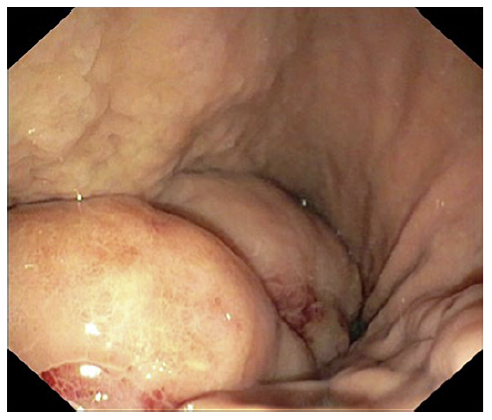

We present a 71-year-old female with no relevant past medical history. The patient was started on a proton pump inhibitor for dyspepsia, with complete symptomatic improvement. One year later, there was symptom recurrence with weight loss. Upper endoscopy revealed a 10 cm gastric subepithelial lesion, with central erosion (Fig. 1). Pathology evaluation was negative for malignancy. Computed tomography showed an extensive gastric wall lesion, with no adenopathies (Fig. 2). Endoscopic ultrasound (EUS) evaluation revealed an 8 cm subepithelial polycyclic hypoechoic lesion, with transition zone suggestive of the third/fourth layer origin (Fig. 3a). Quantitative elastography evaluation showed strain histogram 68 (Fig. 3b). The fine needle biopsy using a 22-G Franseen needle revealed clonal proliferation of plasma cells, positive for CD45/CD138 and negative for CD3/CD20/CD56 (Fig. 4). There was no anemia, hypercalcemia, or kidney impairment, and no abnormalities were found on bone marrow biopsy and myelogram apart from mildly increased plasma cell proliferation (5-10% of total cells). The positron emission tomography/computed tomography scan showed increased gastric uptake, with a maximum standardized uptake value of 3.3. Treatment consisted of surgical resection and the patient had an uneventful postoperative course. The surgical specimen confirmed the diagnosis.

Solitary extramedullary plasmacytomas are plasma cell tumors arising outside of the bone marrow, accounting for approximately 3% of plasma cell malignancies [1]. Within this category, gastric plasmacytoma accounts for less than 2% of extramedullary plasmacytomas [2]. They frequently present as solitary lesions, although sometimes the endoscopic appearance can only reveal erosion of the mucosa [3]. Symptoms are nonspecific, with epigastric discomfort, abdominal pain, nausea, and vomiting commonly reported. Diagnosis requires biopsy-proven extramedullary tumor with evidence of clonal plasma cells, with flow cytometry immunophenotyping assuming a major role in most hematologic malignancies, along with normal skeletal and bone marrow survey and the absence of endorgan damage attributable to the underlying plasma cell disorder [4]. The role of EUS is not standardized, and data are scarce regarding EUS features of a gastric plasmacytoma [5]. Surgery is usually the treatment of choice, with a good prognosis [6]. The authors highlight the EUS role as part of the diagnostic workup of gastric plasmacytoma, a rare clinical entity.